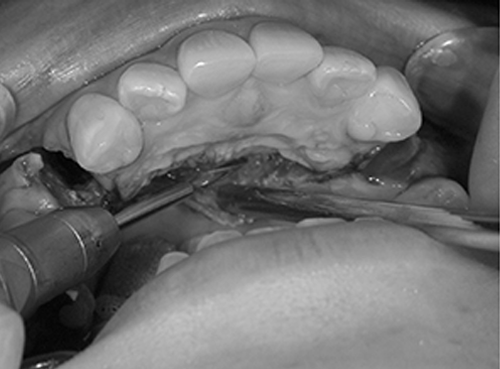

4. 切開します

下のあごの手術を始めます。骨を切って、削って後ろに下げるために必要な範囲を切開します。下くちびるの裏側に3cmくらいの小さな切開をします。薄い粘膜だけを切開します。

切開にはメスや電気メスを使用して、他の組織を傷つけません。切った部分からガーゼを使って優しく手指で伸ばすと、粘膜の下にオトガイ筋、下唇下制筋、オトガイ神経などが透けて見えます。傷つけないように慎重に次の作業に進みます。

5. 剥離します

剥離(はがすこと)は、骨を削るために必要な骨の面が見えるようにおこないます。ガーゼとスプーンのような器具を使って、神経の走行や出口に注意しながら慎重におこないます。骨の膜である骨膜まで剥がすには、まわりにたくさんの筋肉や血管がありますが、傷をつけない様に丁寧に剥がします。

骨膜に到達したら、骨膜はメスを使って切り離します。

骨を切ったり、削除したりする部分だけを露出させます。きれいに骨が露出できれば、骨がきれいに切れて、手術後の出血が少なく、腫れも少なく、治りが早くなります。また、きれいな切開と剥離は、不自然な表情にならないように手術が終わって縫う時に役立ちます。